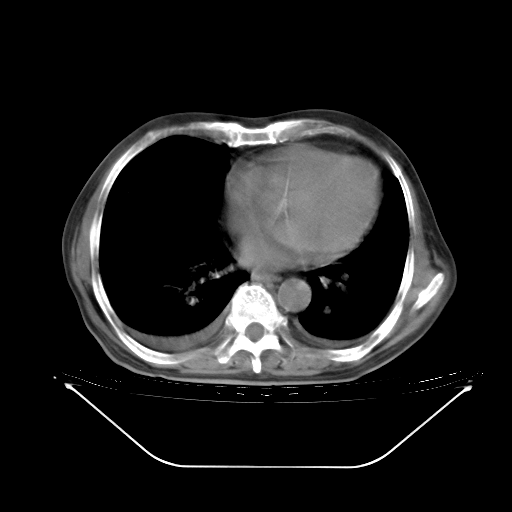

今天复查肺部CT,发现双肺广泛磨玻璃样改变。所以我把3月19日和5月9日相隔50天的肺部CT上传。请大家会诊。

5月9日肺部CT(在4月27日齐鲁医院肺部CT描述部分肺组织磨玻璃样改变,12天后肺组织广泛磨玻璃样改变)

2009年5月9日肺部CT

大致读了系列胸部CT:纵隔窗无明显异常,肺窗:从4、27至今:主要是双肺中下野外带可见毛玻璃样改变,目前处于急性肺泡炎阶段,至于原因考虑1、结替组织或胶原血管性疾病所致?2、恶性疾病如恶组在肺部所致的表现或细支气管肺泡癌?3、药物或其它原因如肺蛋白沉着症所致肺泡炎目前不太可能?总之,明天就去请我院的呼吸科、感染科、血液科和临免专家会诊哈。